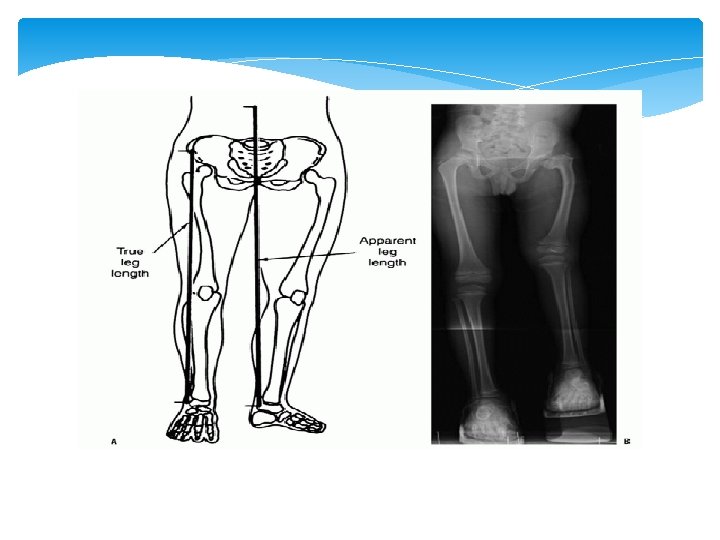

Leg length discrepancy Inequality in leg length is commonly associated with compensatory gait abnormalities and may lead to degenerative arthritis of the lower extremity and lumbar spine. Patients with leg-length discrepancy (LLD) can also have angular and torsional deformities as well as soft tissue contractures of the ipsilateral or contralateral extremity that may influence their functional leg lengths.

Leg length discrepancy For instance, flexion contractures around the knee and hip can cause apparent shortening of the leg while abduction contractures of the hip and equinus deformity of the ankle tend to functionally lengthen the affected extremity. Besides clinical evaluation, there are several imaging modalities that have been described to quantify LLD. The use of appropriate clinical methods and imaging modalities for measuring the LLD is vital to properly treat a patient with unequal leg lengths or related symptoms.

Leg length discrepancy Difference Clinical Techniques for Assessing Leg-length 1 - Tape measure: A tape measure is typically used to measure the length of each lower extremity by measuring the distance between the anterior superior iliac spine (ASIS) and the medial malleolus and is referred to as the ‘‘direct’’ clinical method for measuring LLD. However, differences in the girth of the two limbs, and difficulty in identifying bony prominences as well as angular deformities can contribute to errors using this clinical measurement tool.

Leg length discrepancy Types A- anatomical (true): structural limb length inequality. It’s a physical (osseous) shortening of one lower limb between the trochanter femoral major and the ankle mortise. Congenital conditions include mild developmental abnormalities found at birth or childhood, whereas acquired conditions include trauma, fractures, orthopedic degenerative diseases and surgical disorders such as joint replacement. A systemic review evaluating the prevalence of LLD by radiographic measurements revealed that 90% of the normal population had some type of variance in bony leg length, with 20% exhibiting a difference of >9 mm

Leg length discrepancy Types A-functional : non-structural shortening. It is a unilateral asymmetry of the lower extremity without any shortening of the osseous components of the lower limb. FLLD may be caused by an alteration of lower limb mechanics, such as joint contracture, static or dynamic mechanical axis malalignment, muscle weakness or shortening. It is impossible to detect these faulty mechanics using a nonfunctional evaluation, such as radiography. FLLD can develop due to an abnormal motion of the hip, knee, ankle or foot in any of the three planes of motion